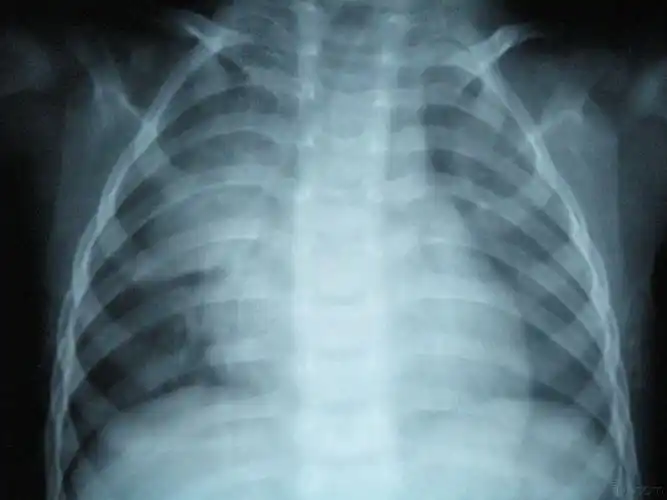

这几组患儿胸片是肺炎还是正常影像规培医师懵了

宝宝五个月咳嗽有痰鼻子不通气,今天去拍的胸片,希望医生看看